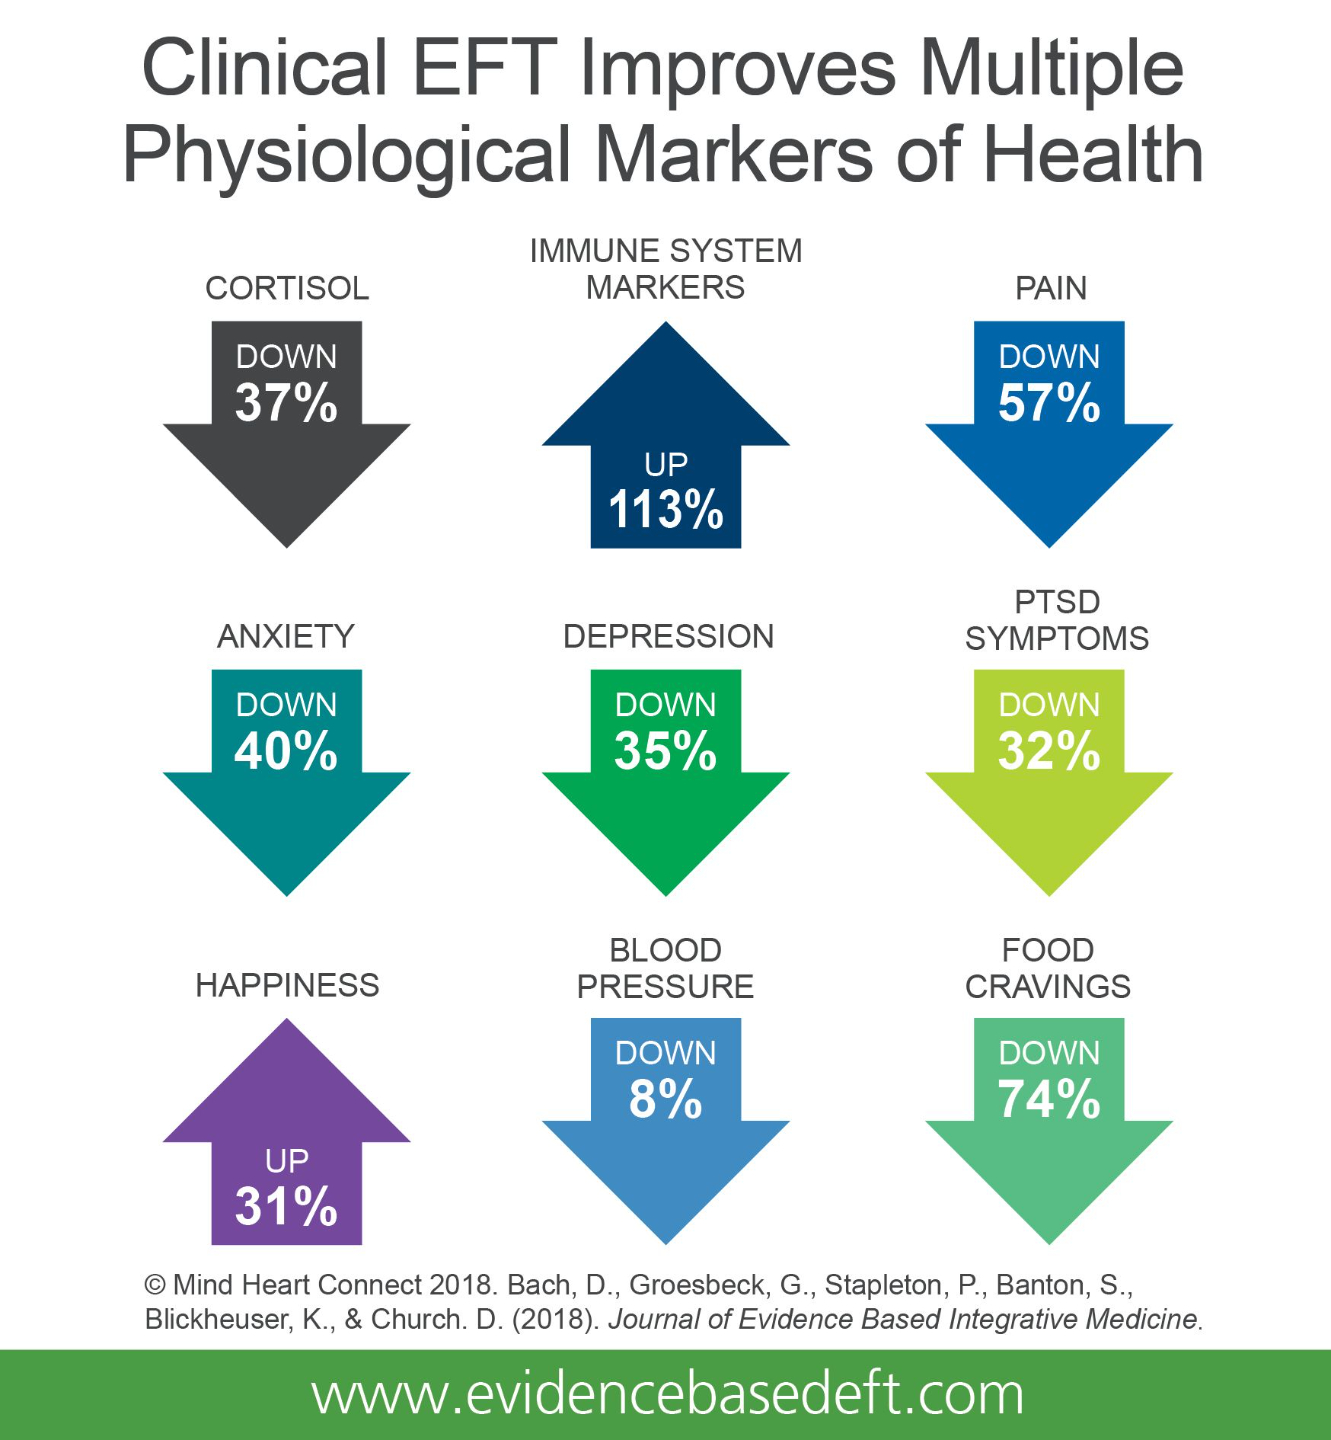

4) It improves multiple physiological Markers of health